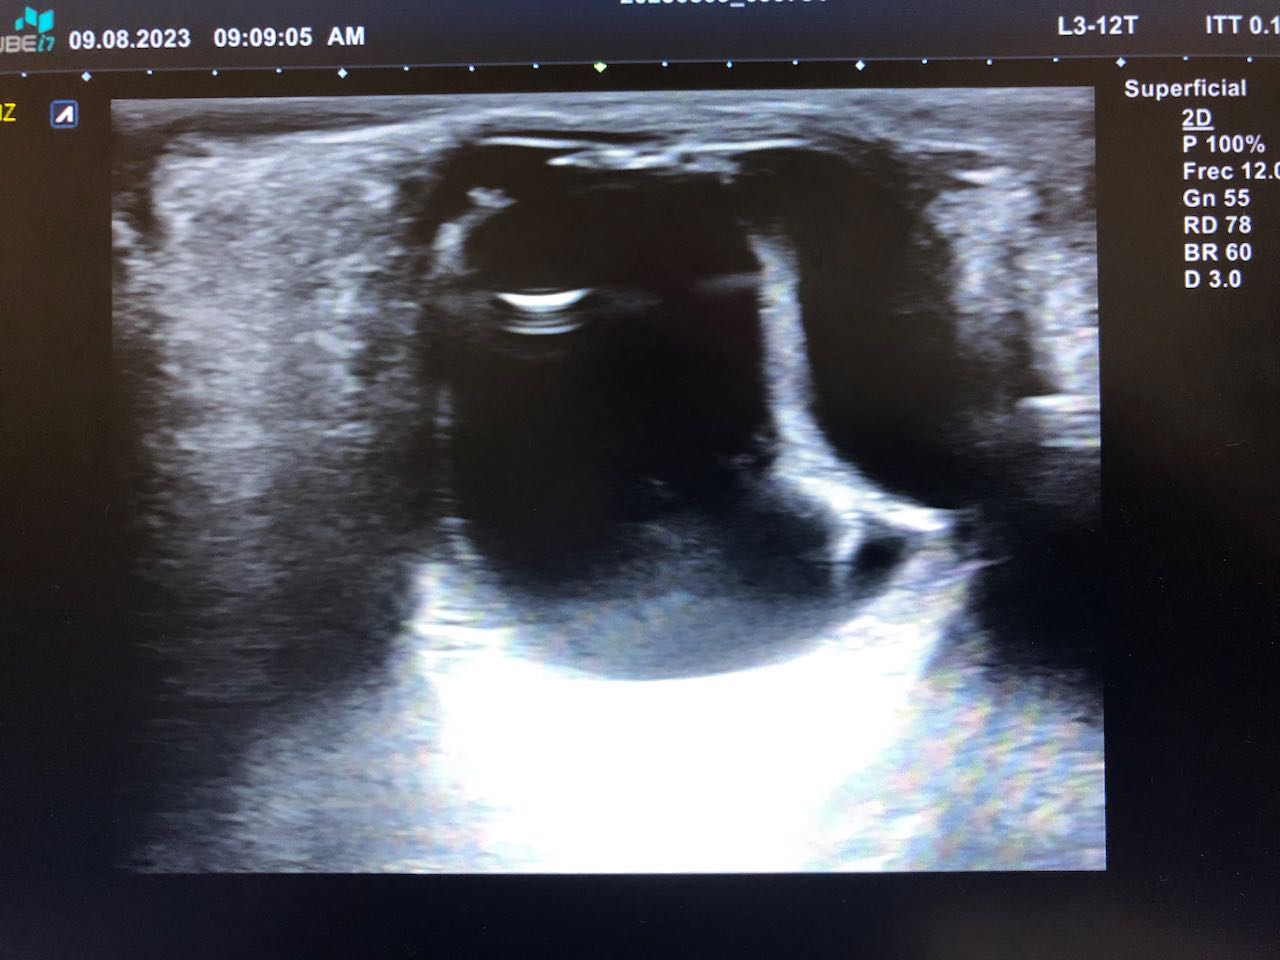

Citado en cita forzada, refiere molestias oculares, con sensibilidad a la luz, que le obliga a mantener el ojo cerrado, acude por precisar gotas para la conjuntivitis, ante la dificultad idiomática y considerar que el paciente es poco preciso en la descripción de los síntomas, pues ante la pregunta de «si tiene dificultades en la visión» el paciente se reitera que le molesta muy cierra el ojo, y en relación con el dolor que es como si tuviera algo que le roza. Se procede a la exploración ocular, observando un ojo derecho normal con blefaroespasmo en ojo izquierdo (OI), hiperemia ocular tarsal, con pupilas reactivas, fluortest negativo y presión intra ocular (medición palpebral), normal en los dos ojos. Ante la incongruencia de la sintomatología referida y los hallazgos exploratorios, se considera indicado hacer una ecografía ocular, en la que se apreció signos de desprendimiento de retina y coroides del OI.

Se confirma desde Oftalmología el diagnóstico: Desprendimiento de retina casi completo junto a desprendimiento de Coroides temporal en OI de contenido hiperecogénico, no se aprecian masas.